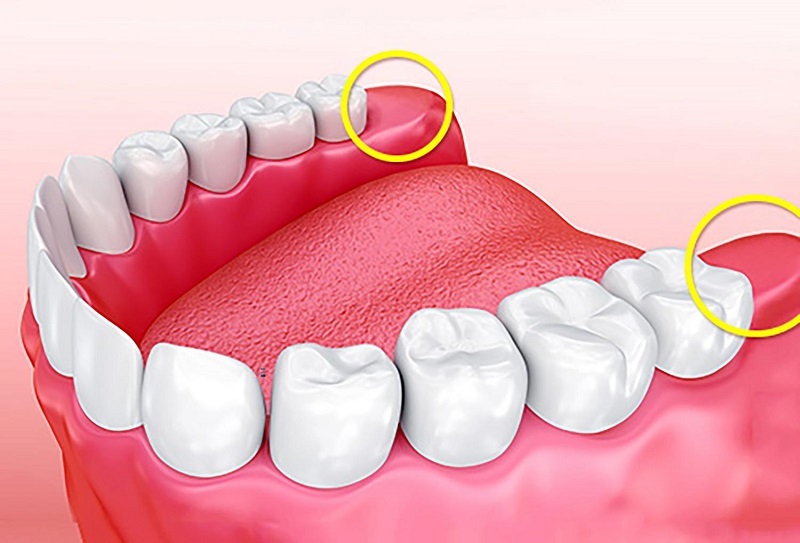

Что такое ретинированный и дистопированный зуб мудрости?

Ретинированный — непрорезавшийся зуб, он полностью скрыт под десной. Не до конца прорезавшийся зуб называют «полуретинированным». Опасность ретенции заключается в том, что при прорезывании моляра может развиться воспаление десны.

Дистопированный — аномально расположенный зуб. Он либо прорезался не на своём месте, либо развился под неправильным углом (наклонен в сторону), либо повёрнут вокруг своей оси. В стоматологической практике наблюдались аномалии, когда дистопированные зубы росли корнями вверх.

Зуб мудрости может расти как с одним из этих дефектов, так и сразу с двумя. Ретенция и дистопия, как правило, сопровождаются воспалением десны, отёком мягких тканей и другими малоприятными симптомами. Худший вариант развития событий — смещение зубного ряда и, как следствие, длительное и дорогостоящее лечение у ортодонта.